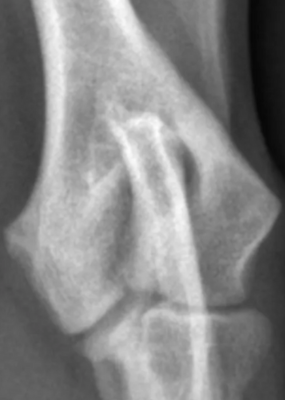

2. Radiographies du coude

Souvent le premier examen réalisé. Elles peuvent révéler :

- une fine ligne radiotransparente entre les condyles huméraux

- Une réaction périostée sur la crête épicondylaire latérale

- des signes d’arthrose précoce.

Plusieurs vues sont réalisées comprenant une face classique craniocaudal, une vue latérale en flexion, une vue oblique craniomédiale à caudolatérale avec une rotation de 15 degrés.

Cependant, la fissure peut être trop fine pour être visible.